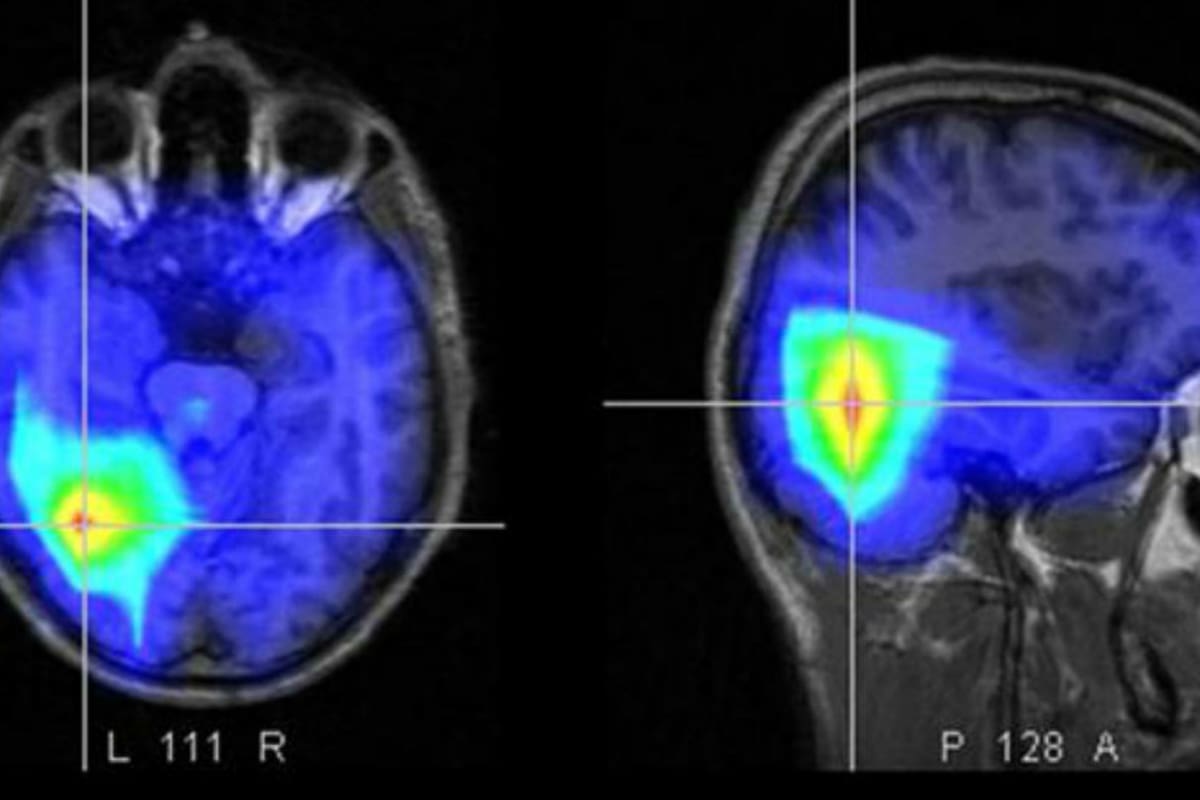

Las zonas del cuerpo más comunes en las que se desencadena el aneurisma son la aorta abdominal o torácica, la arteria poplítea (en las piernas por detrás de las rodillas), el cerebro, la arteria esplénica (en el brazo) y la arteria mesentérica (en el intestino).

En términos médicos, un aneurisma es una dilatación permanente y localizada alojada en las paredes de las arterias del cuerpo. Es la consecuencia de una gran debilidad en alguna zona de un vaso sanguíneo.